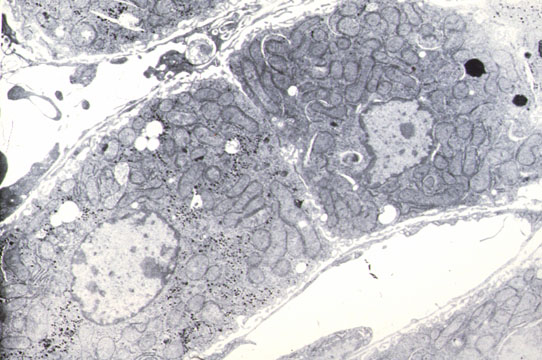

Fig 8 - BILE CANALICULI

They drain bile from the hepatocytes to the portal space. Microscopically visible only when distended by bile. Can also be demonstrated by Gomori's reaction for alkaline phosphatase and silver impregnation. Their wall is made by the plasma membrane of two adjacent hepatocytes which form intracanalicular villi. They form an intricate anastomotic network of canals.